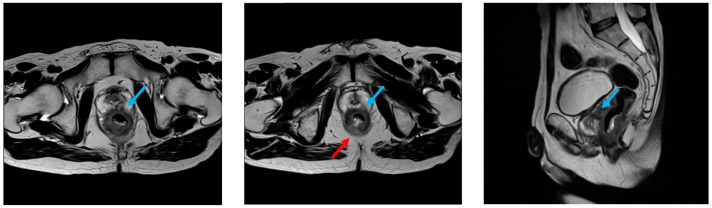

全盆腔切除(TPE)是一种根治性手术,用于晚期盆腔恶性肿瘤累及邻近器官。Hugo™RAS系统是一种新颖的机器人平台,但其在TPE中的应用此前尚未报道。我们描述了第一例使用Hugo™RAS进行机器人辅助TPE的患者,该患者局部晚期直肠癌侵犯前列腺。方法:69岁男性,以黏液及血便诊断为cT4b(前列腺提肛肌)N0M0直肠癌。在短期放疗(25 Gy/5次)后,进行机器人辅助TPE。端口放置计划与未来结肠造口和尿造口的位置一致,以尽量减少腹壁创伤。完成了整体切除,随后用臀大肌皮瓣和自体阔筋膜移植重建盆腔。通过机器人体内华莱士型回肠导管完成尿分流。结果:手术时间17 h 56 min,出血量175 mL。术后发生Clavien-Dindo IIIa级麻痹性肠梗阻,但予以保守处理。病理显示pT4b(前列腺)N1a M0病变,周缘阴性(11 mm)。9个月无复发。结论:该病例强调了Hugo™ras辅助TPE的技术可行性和安全性。需要进一步的临床经验来确认可重复性和肿瘤安全性。

Introduction: Total pelvic exenteration (TPE) is a radical procedure for advanced pelvic malignancies involving adjacent organs. The Hugo™ RAS System is a novel robotic platform, but its application in TPE has not previously been reported. We describe the first case of robotic-assisted TPE using Hugo™ RAS in a patient with locally advanced rectal cancer invading the prostate. Methods: A 69-year-old male with mucous and bloody stools was diagnosed with cT4b (prostate, levator ani muscle) N0M0 rectal cancer. After short-course radiotherapy (25 Gy/5 fractions), robotic-assisted TPE was performed. Port placement was planned to coincide with future colostomy and urostomy sites to minimize abdominal wall trauma. En bloc resection was achieved, followed by pelvic reconstruction with a gluteus maximus musculocutaneous flap and fascia lata autograft. Urinary diversion was completed with a robotic intracorporeal Wallace-type ileal conduit. Results: The operation lasted 17 h 56 min, with 175 mL blood loss. Postoperatively, Clavien-Dindo grade IIIa paralytic ileus occurred but was managed conservatively. Pathology revealed pT4b (prostate) N1a M0 disease with negative circumferential margin (11 mm). No recurrence was observed at 9 months. Conclusions: This case highlights the technical feasibility and safety of Hugo™ RAS-assisted TPE. Further clinical experience is needed to confirm reproducibility and oncologic safety.